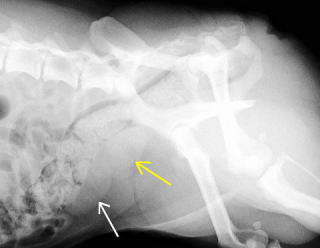

患者さんは未去勢雄、5歳のコーギーです。血尿が続いたため、当院を受診されました。初診時の尿検査で、色調は正常であったにもかかわらず、強い潜血反応を認め、塗抹でも赤血球を多数認めました(表参照)。前立腺肥大を疑い、肛門より触診を実施しました。その結果、表面がスムースでプクンとした感じの前立腺が触知され、レントゲン検査でも、前立腺の肥大を示す陰影を認めたことから(写真参照)、前立腺肥大と診断しました。

膀胱(矢印白)の上に、腫大した前立腺(矢印黄色)が認められます。